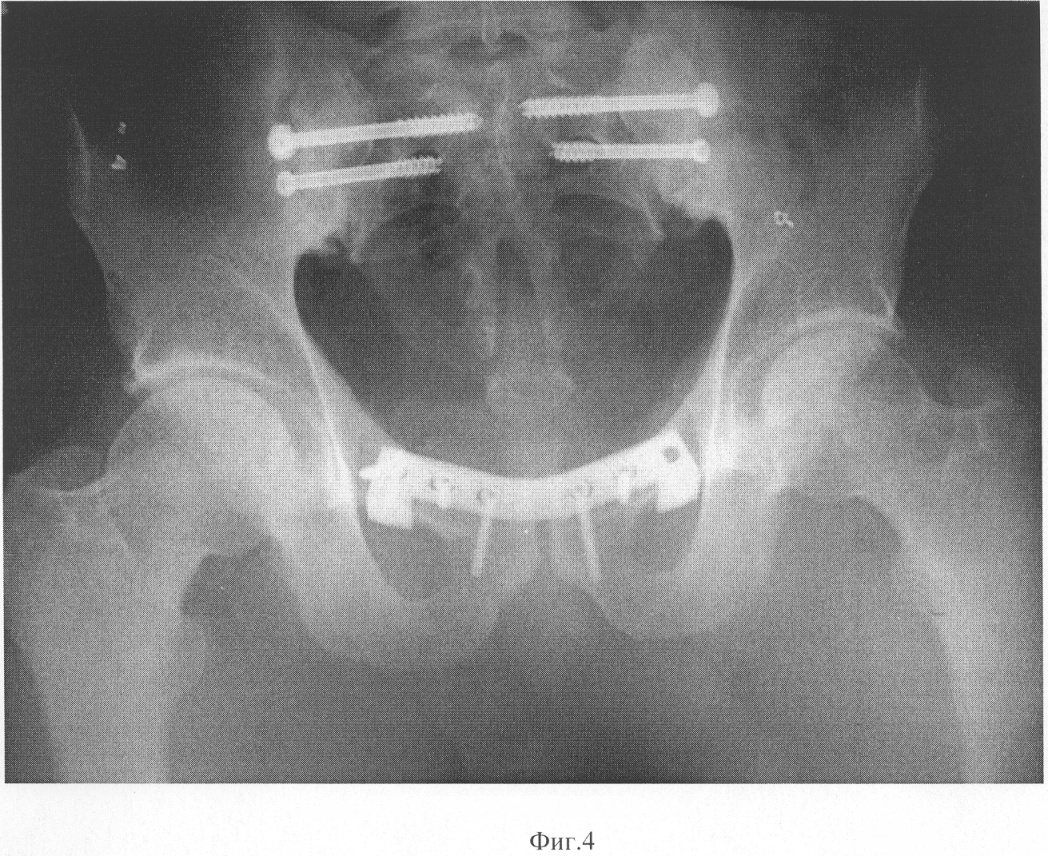

На фиг 4 приведен рентгеновский снимок, сделанный при проведении операции на лонном сочленении.